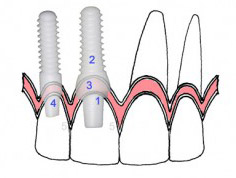

همان گونه که از نام این سری از انواع ایمپلنت مشخص است، در ایمپلنتهای یک مرحلهای ایمپلنت و اباتمنت (اتصال دندان پروتزی با تاج دندان مصنوعی) به طور همزمان درون لثه و استخوان فک نصب میشود. بر همین اساس نیازی به انجام جراحی دو مرحلهای نیست و این ویژگی تا حد زیادی موجب کاهش مدت زمان نصب ایمپلنتها میگردد. اما همواره توجه داشته باشید که این مدل از انواع ایمپلنت دندان حساسیت بالایی دارد و عدم نصب صحیح آن موجب آسیبهای فشاری به لثه و استخوان فک میشود. بنابراین حتیالامکان برای کاشت ایمپلنت یک مرحلهای به متخصص ایمپلنت مراجعه نمایید.

این مدل نیز یکی از رایجترین و متداولترین روشهای کاشت ایمپلنت دندان محسوب میشود. بدین منظور ابتدا بافت لثه شکافته شده و یک سوراخ ریز درون استخوان فک ایجاد میکنند. پس از انجام این مرحله، پایه تیتانیومی ایمپلنت درون استخوان فک قرار میگیرد. در ادامه برای کاهش مدت زمان ورم لثه، با بخیه اطراف آن بسته میشود. در پایان نیز پس از بهبود جراحی اول، با جراحی و ایجاد برش در نواحی کاشت پایه، اتصال تاج دندان و ایمپلنت صورت میگیرد. تاج یا روکش می تواند از نوع روکش زیرکونیوم نیز باشد که با نظر متخصص بهترین روکش ایمپلنت دندان باید انتخاب شود.

bone level به ایمپلنتهایى گفته مىشود که سطح کاشت ایمپلنت هم سطح با استخوان بیمار قرار مىگیرد و مىتوان از درمان یک مرحلهاى و یا دو مرحلهاى بهره جست و به سه دسته تقسیم مىشود.

miniimplants-Tissue level با ایمپلنتهایى اطلاق مىشود که سطح کاشت ایمپلنت به جاى هم سطح بودن با استخوان؛ با لثه هم سطح مىشود و طبیعتا درمان یک مرحلهاى صورت مىگیرد.